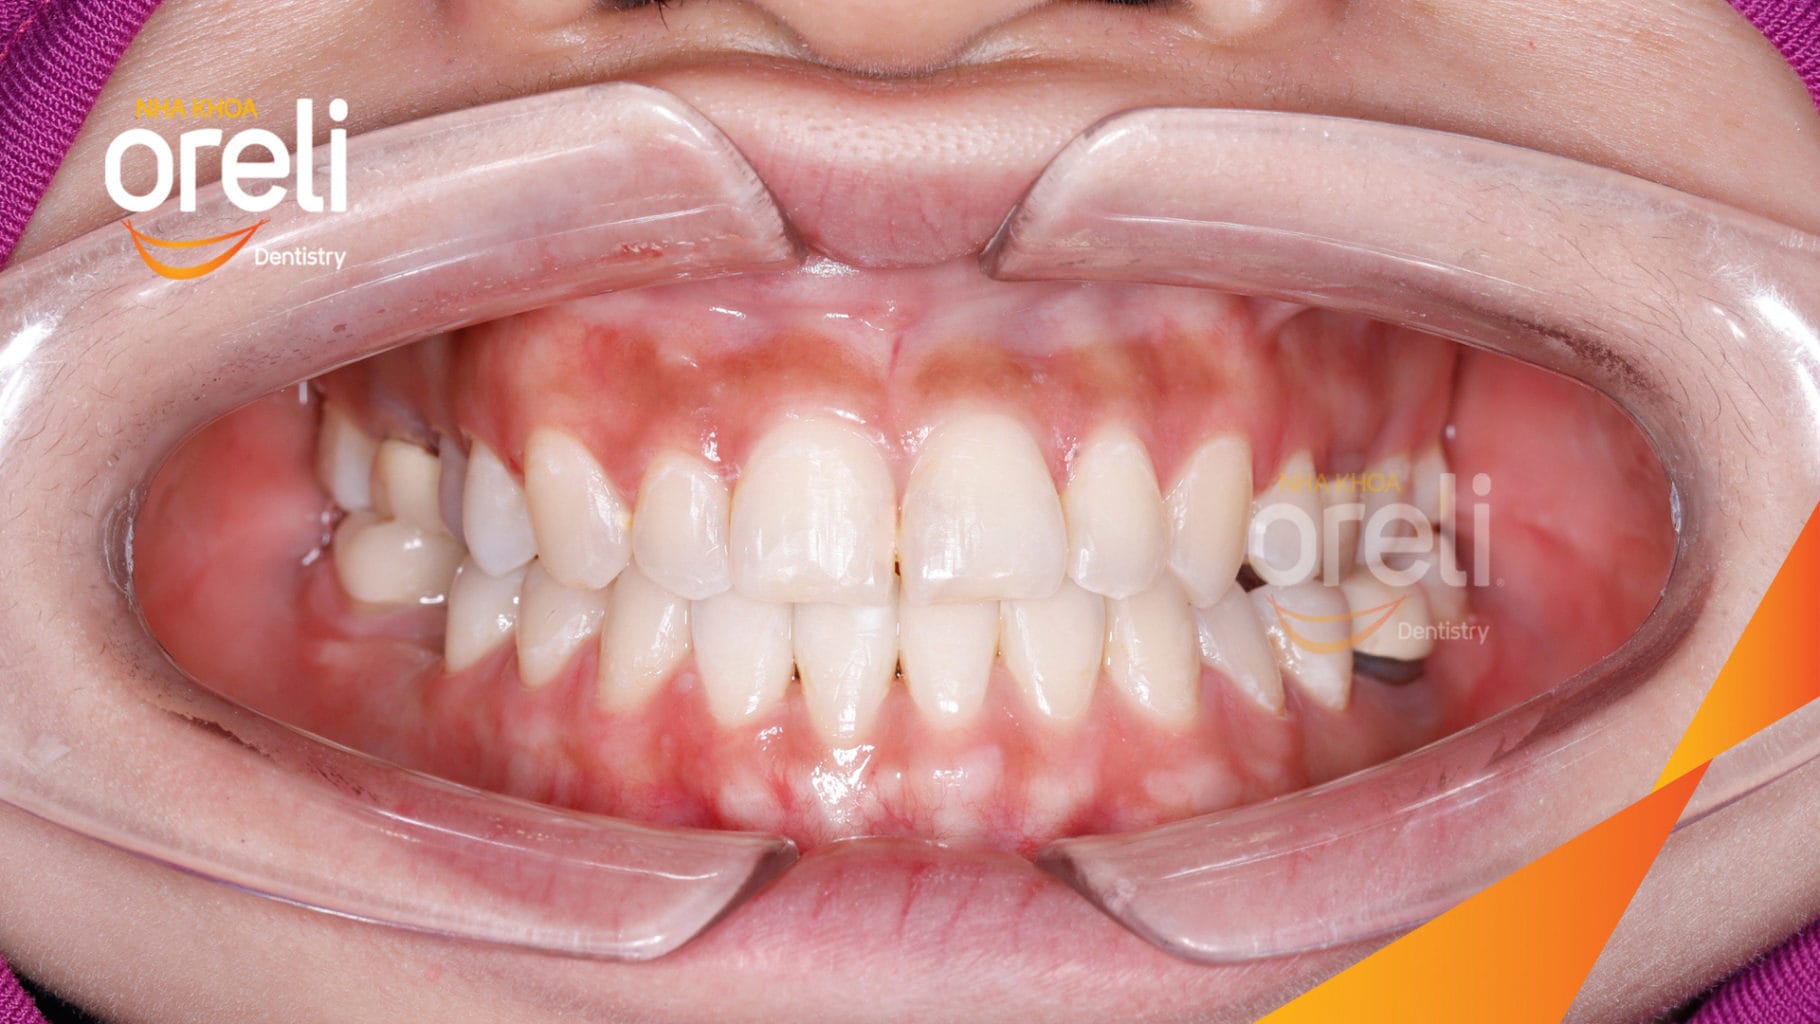

Ca niềng hạng 3 móm di gần răng 78 cho nụ cười đẹp ở Oreli

Ca niềng răng di gần răng 7 8 phục hồi ăn nhai và thẩm mỹ nụ cười. Kết quả thực tế trước và sau điều trị tại Nha khoa Oreli.